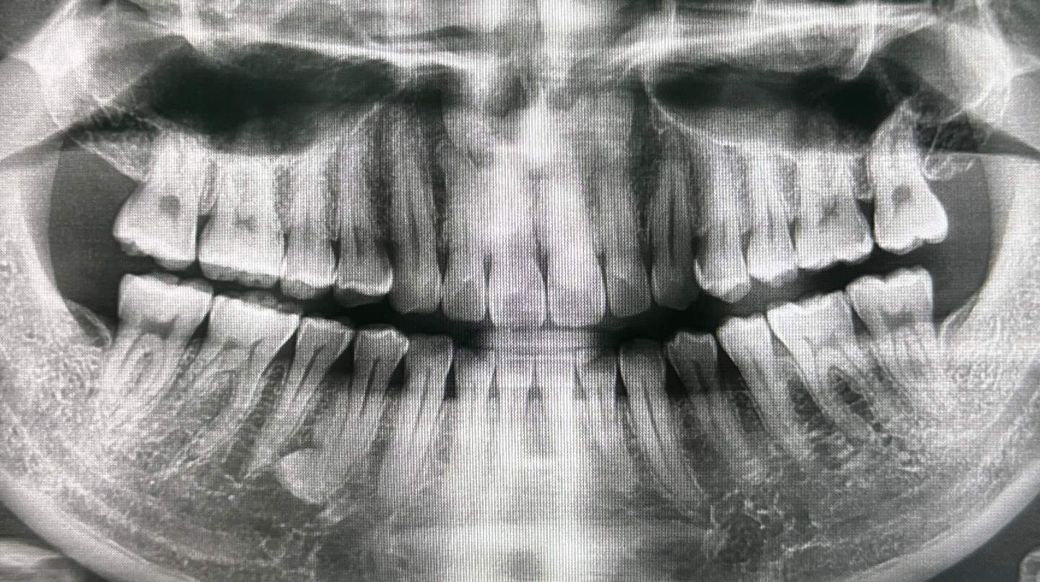

약 2주전 찬바람, 찬물이 닿으면 시려서 치과를 방문하였고 엑스레이 2번 찍었는데 첫번째는 전체적인 엑스레이, 두번째 사진은 왼쪽 치아만 찍은 엑스레이입니다.

엑스레이 결과 염증은 없고, 왼쪽 위 뒤에서 첫번째, 두번째 치아 충치가 의심되지만 애매해서 정기검진때 확인해보자하여 알겠다하였으며, 후에 치경부 마모증으로 인한 시림이라고 레진을 받았습니다.